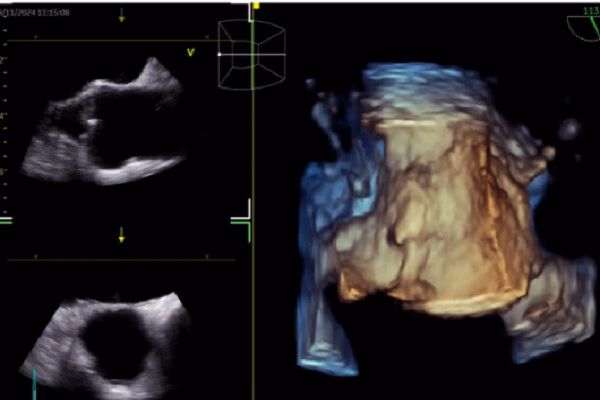

Theo bác sĩ Nhật, hình ảnh học tim mạch là một trong những lĩnh vực có nhiều nghiên cứu và ứng dụng AI nhất. Các ứng dụng này bao gồm điện tâm đồ (ECG), siêu âm tim, CT tim, MRI tim, đặc điểm lâm sàng, tiên lượng và quyết định lâm sàng. AI đã được ứng dụng trong ECG để dự đoán rung nhĩ, suy tim có phân suất tống máu giảm và hẹp van động mạch chủ. Trong siêu âm tim, AI giúp nhận diện cấu trúc cơ tim, đo đạc tự động và hỗ trợ báo cáo và chẩn đoán.